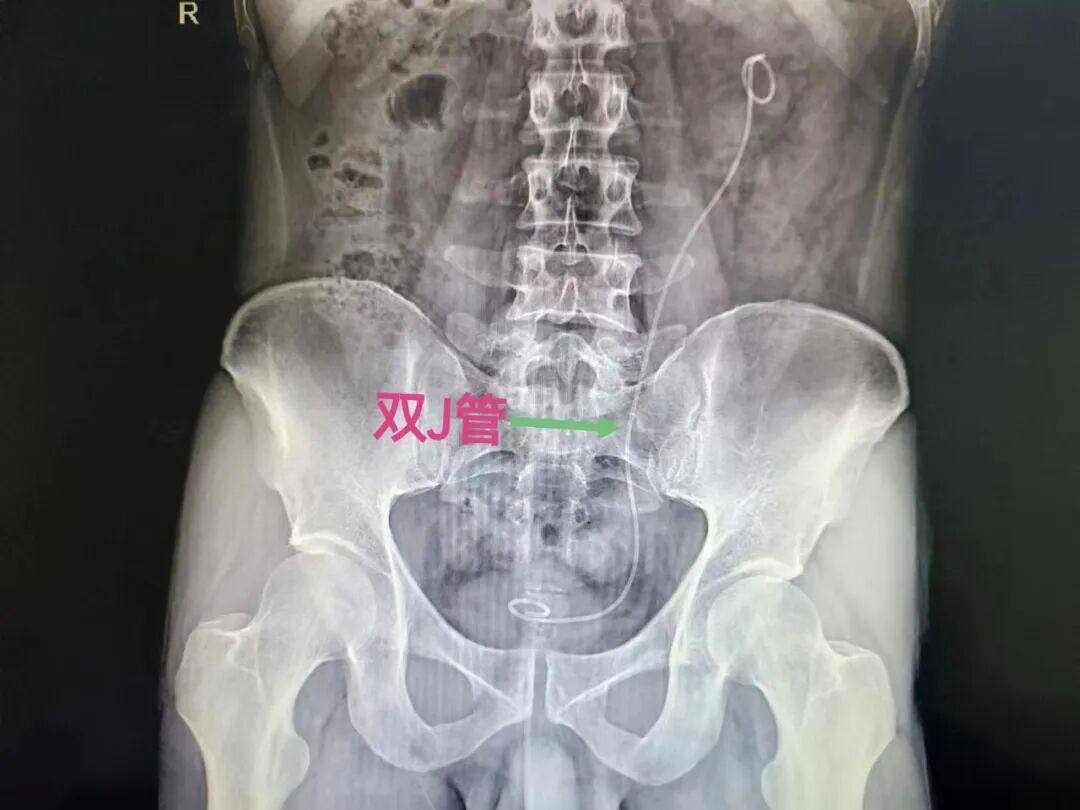

双J管又称输尿管支架管,是一根细长的两头弯曲的软管,弯曲的一端位于肾盂,一端位于膀胱,用以支撑于输尿管内,使尿液正常排出,因两端卷曲形似英文字母“J”,故称为双“J”导管。

(双J管在体内的正常位置)